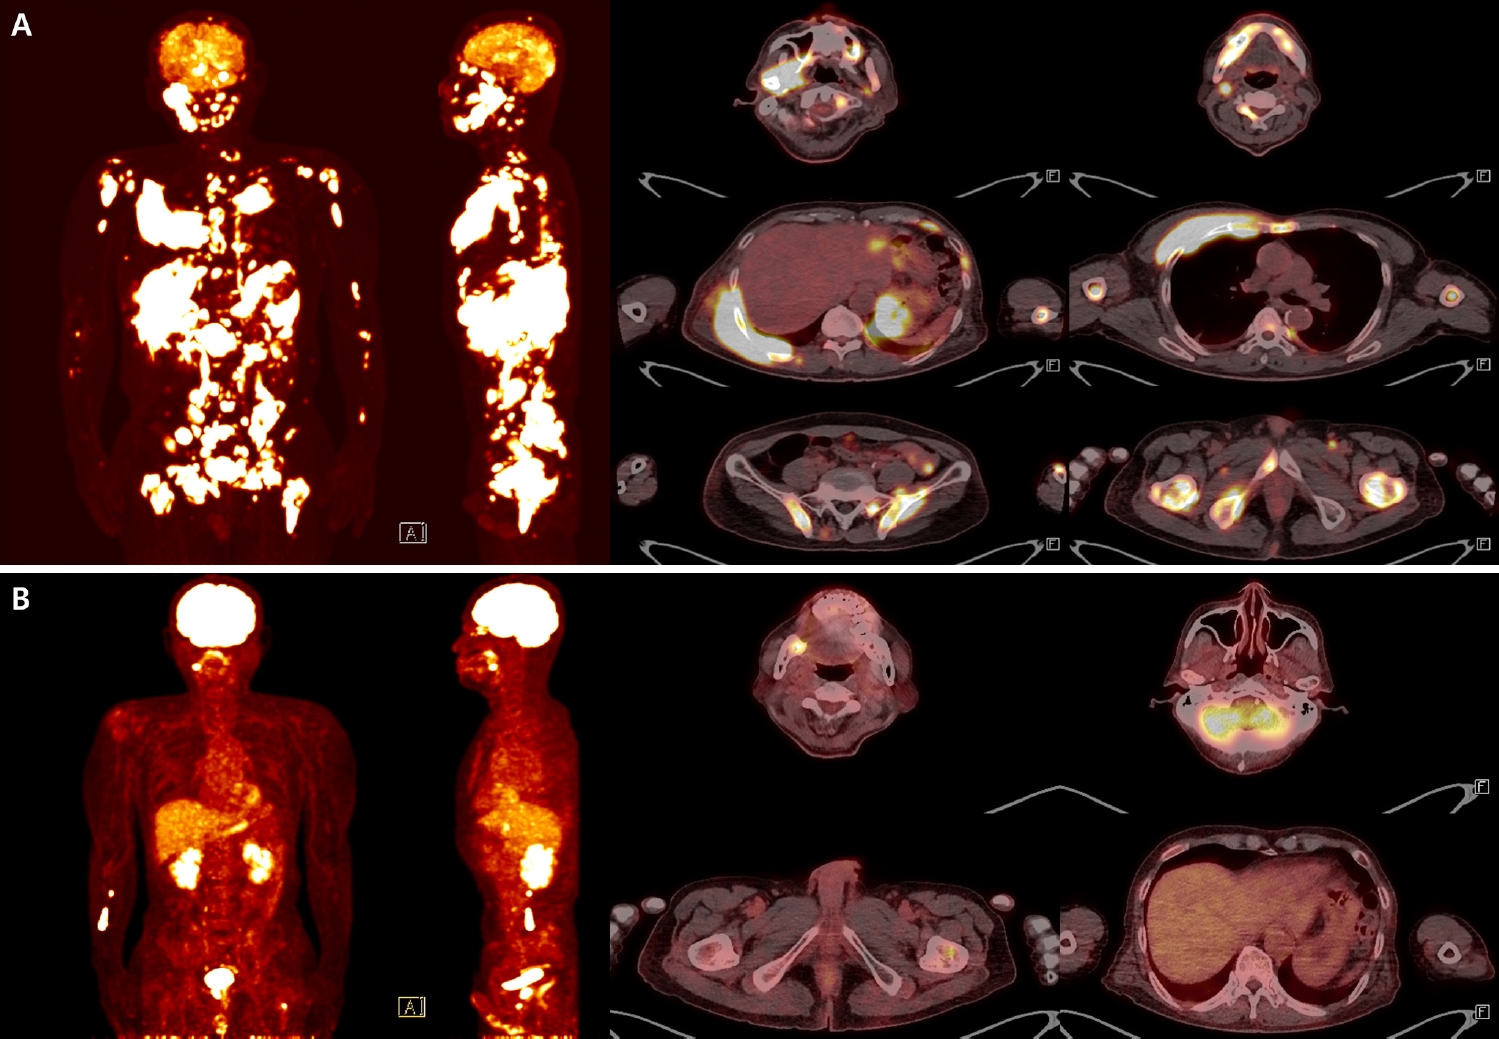

One month later, follow-up CT revealed cortical erosion of the right mandibular condyle, increased bone marrow attenuation, and swelling of the right lateral pterygoid muscle. Magnetic resonance imaging further showed diffuse hyperintensity of the mandibular body marrow and perimandibular soft tissues on T2-weighted images, with extension to the mandibular foramen and condyle. Marked swelling and diffusion restriction of the lateral pterygoid muscle were also noted, suggestive of progressive inflammation (Fig. 2).

Fig. 2.

Follow-up computed tomography (CT) and magnetic resonance imaging (MRI) imaging showing progressive bony and soft tissue changes. Axial CT image obtained 1 month after initial presentation shows cortical erosion of the right mandibular condyle and increased bone marrow attenuation in the right mandibular ramus. T2-weighted MRI reveals diffuse hyperintensity in the mandibular marrow and surrounding soft tissues and restricted diffusion in the right lateral pterygoid muscle. No distinct mass lesion is identified, despite these progressive changes. Arrows indicate cortical erosion, arrowheads indicate increased attenuation of bone marrow and periosteum, and asterisks indicate swelling of lateral pterygoid muscle.

Fig. 2. Follow-up computed tomography (CT) and magnetic resonance imaging (MRI) imaging showing progressive bony and soft tissue changes. Axial CT image obtained 1 month after initial presentation shows cortical erosion of the right mandibular condyle and increased bone marrow attenuation in the right mandibular ramus. T2-weighted MRI reveals diffuse hyperintensity in the mandibular marrow and surrounding soft tissues and restricted diffusion in the right lateral pterygoid muscle. No distinct mass lesion is identified, despite these progressive changes. Arrows indicate cortical erosion, arrowheads indicate increased attenuation of bone marrow and periosteum, and asterisks indicate swelling of lateral pterygoid muscle.